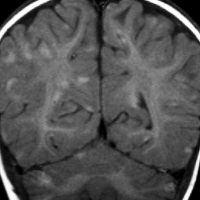

けいれん発作だけで発症した例

脳表のくも膜下腔がガドリニウム造影剤で白く造影されます。これはくも膜下腔ではなくて軟膜のメラノーシスが増強されているものです。髄液播種とは髄腔の見え方が少し違います。